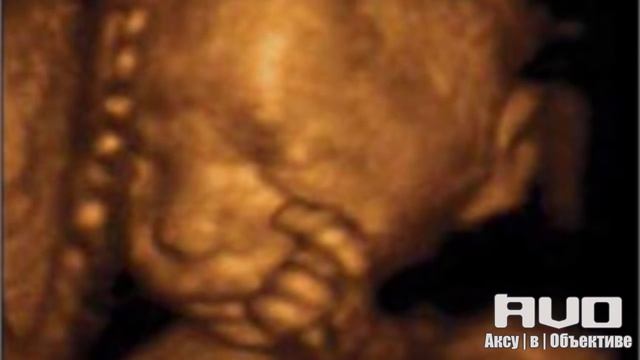

AVO ~ Рекомендует! Проблема абортов смотреть онлайн

14:29

AVO ~ Рекомендует! Проблема абортов

Божественное руководство через молитву 17 просмотров